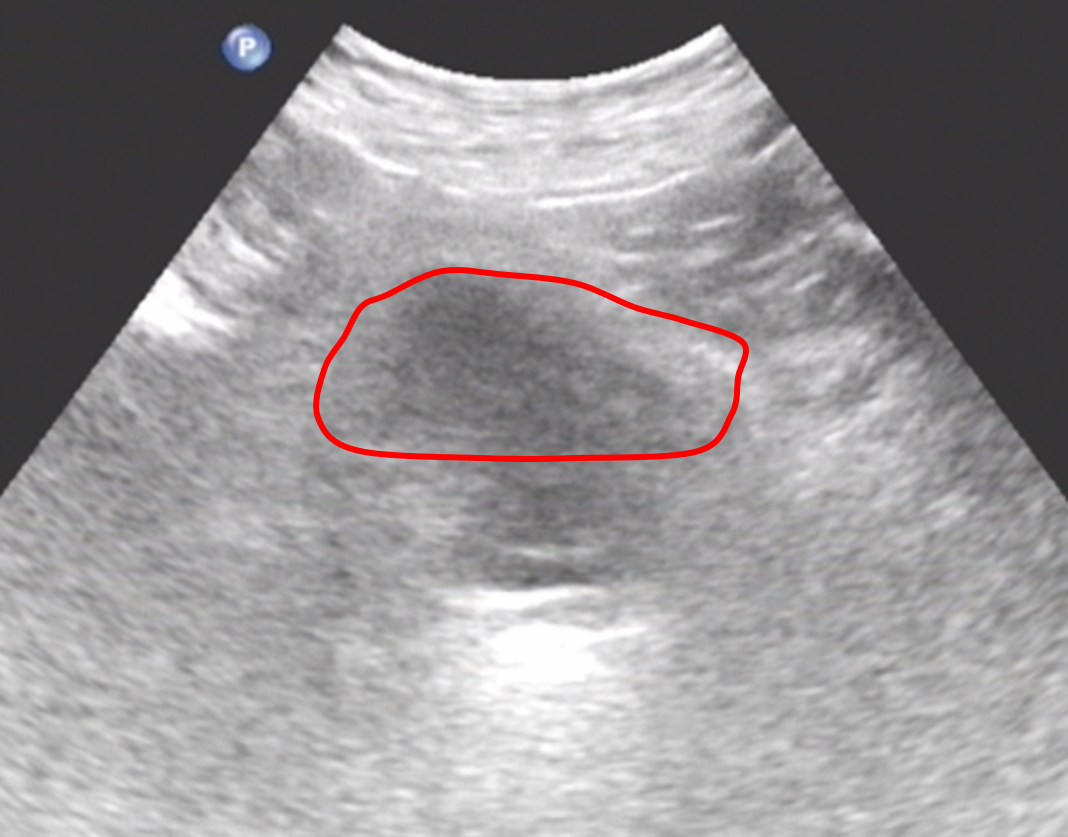

憋尿可充盈膀胱,和胆囊一样在充盈状态,壁薄而光滑,超声图像显示清晰

膀胱充盈差

需要憋尿适度充盈膀胱,以减少肠管气体干扰,并提供良好透声窗